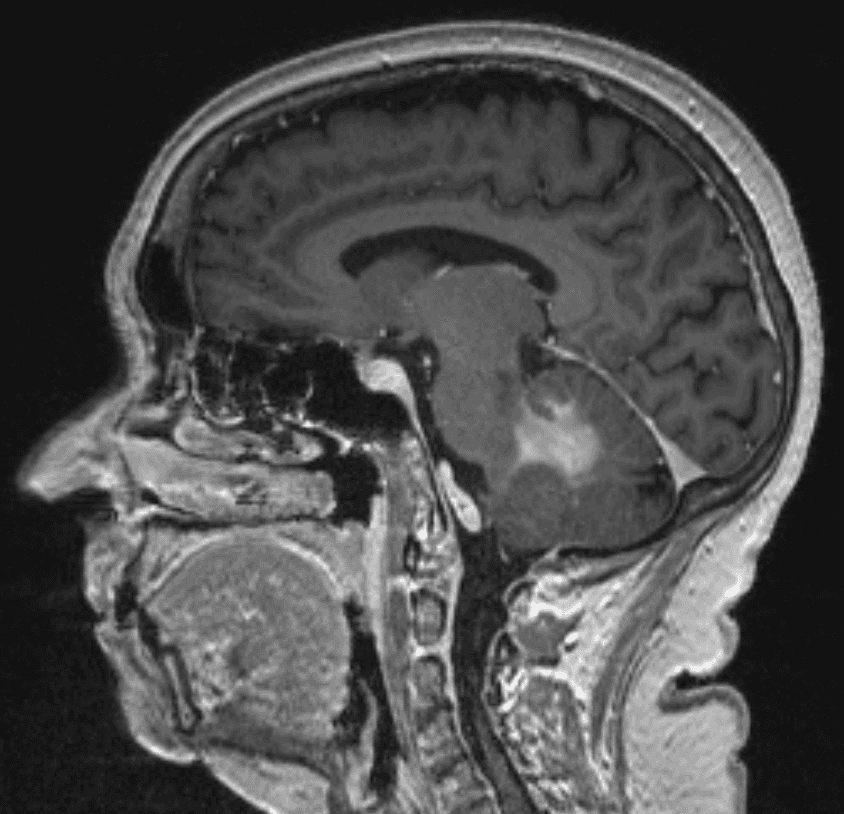

Ha effettuato una risonanza magnetica che ha mostrato una lesione omogenea con contrasto adiacente al quarto ventricolo nel tessuto cerebellare e un edema perifocale moderato (Figure 1–2). I peduncoli del tronco encefalico e cerebellari non erano coinvolti. Non sono stati rilevati segni di emorragia o ischemia.

Figura 1. Queste immagini ponderate T1 potenziate dal gadolinio mostrano una lesione infratentoriale nel cervelletto e nel peduncolo cerebellare sinistro adiacente al quarto ventricolo. Si prega di notare l'aumento omogeneo del contrasto sospetto di linfoma del SNC e mancanza di infiltrazione del tronco encefalico.